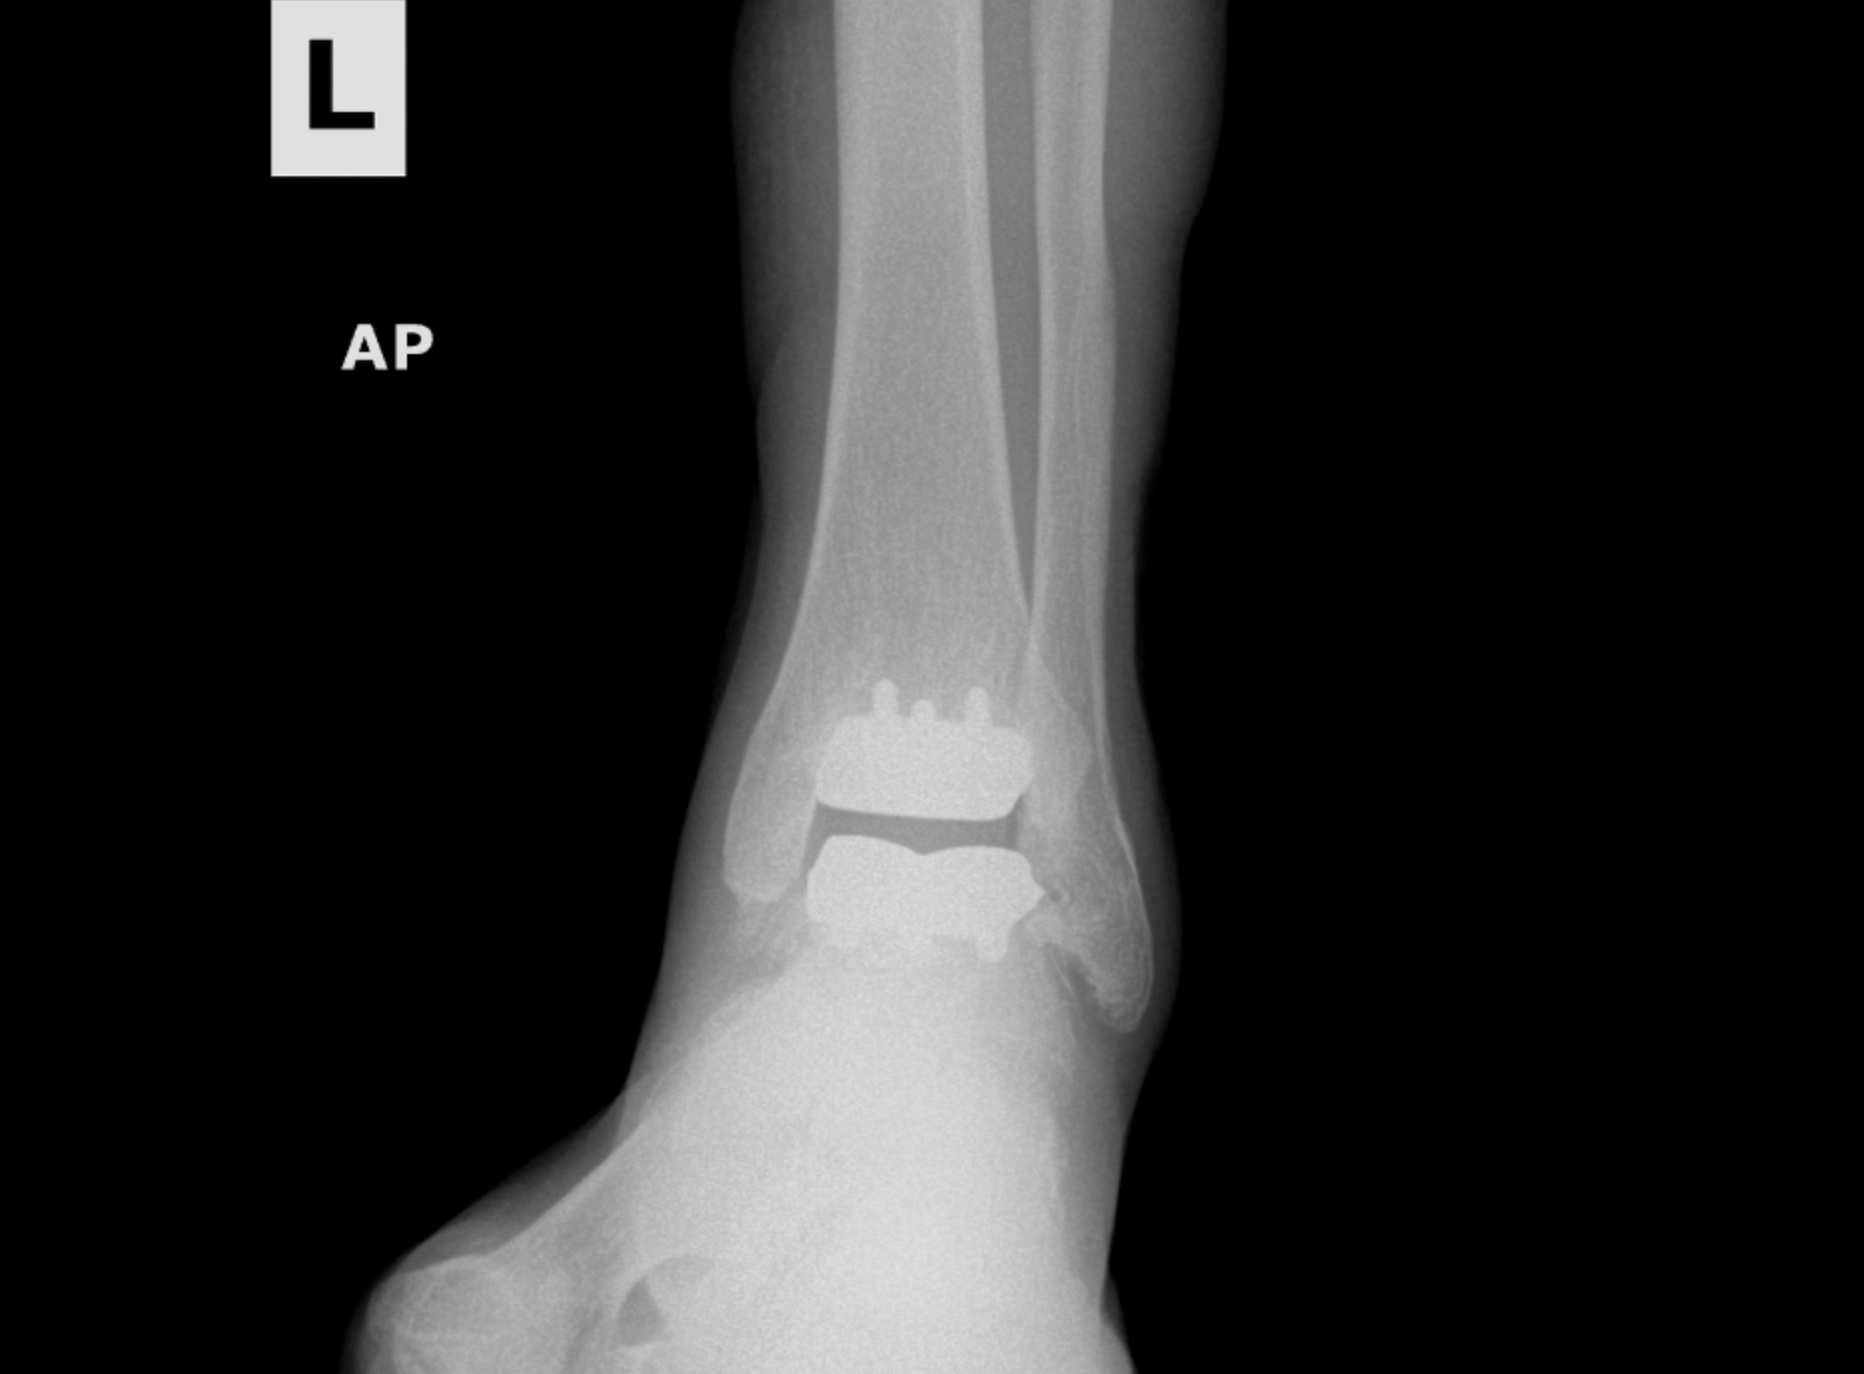

Foot & Ankle Replacement

Coming Soon